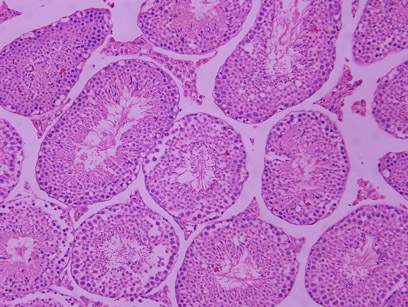

谁能帮忙看一下这几张组织的片子有什么病变没有 已有3人参与